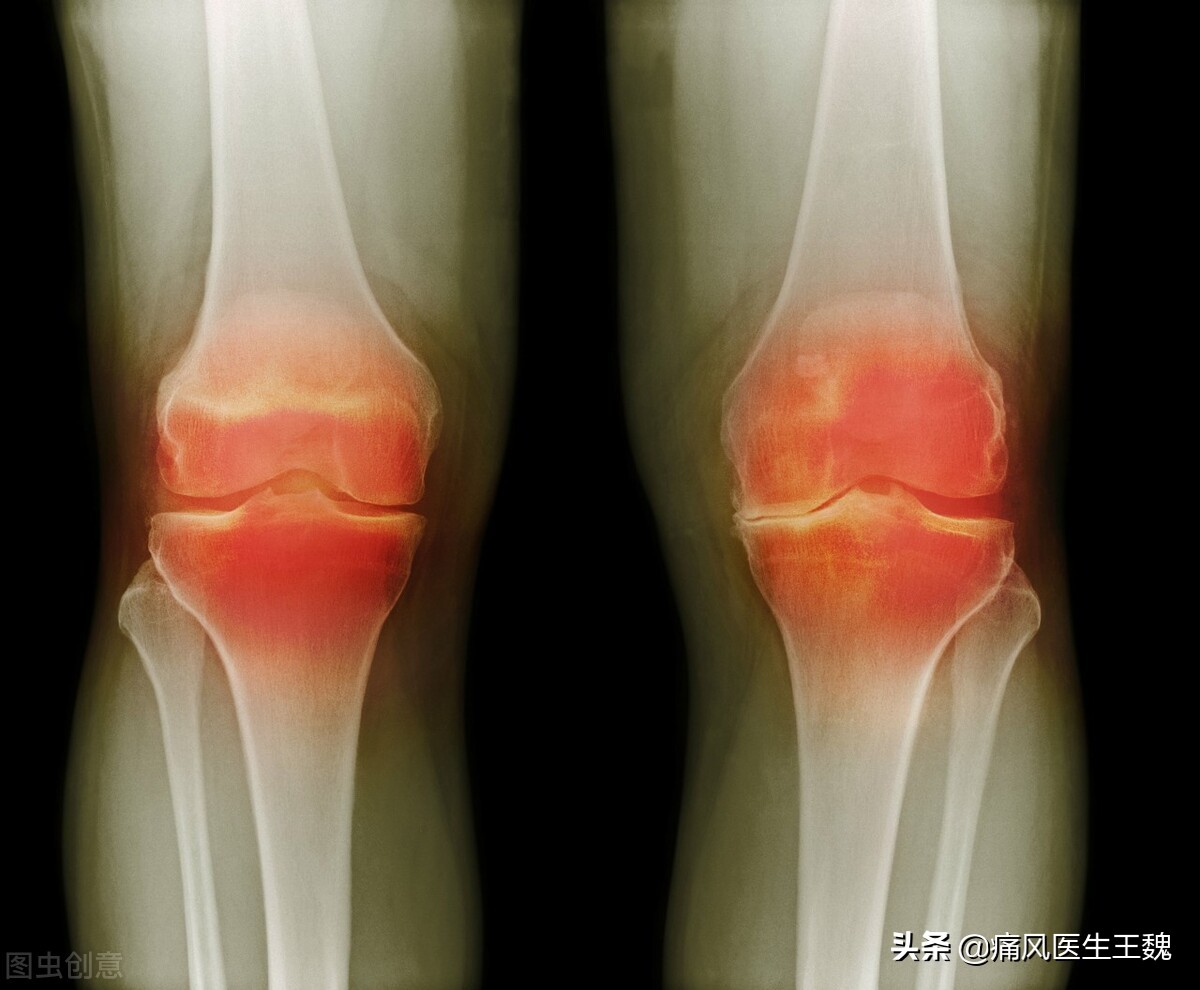

许多痛风患者在确诊后还不对自己的饮食习惯加以控制,使病情越来越严重,发展成痛风石。市民许先生就是一个例子,他在得了痛风后仍然大吃大喝,导致脚上长出痛风石。一开始还很小的痛风石,后来竟长到了馒头大小,大脚趾的外侧开始破溃,并出现了化脓。拍片结果出来后,在场的医护人员更是吃了一惊:病人患处及周围的骨头,都已经被痛风石“吃”掉了!在这种情况下,想保住脚真是难上加难。那么,痛风石是如何“啃噬”骨头,导致患者残疾的?能不能彻底治愈呢?

很多痛风患者没有对待痛风疾病,任其病情延续发展,由急性转为慢性,由慢性到痛风石增生,痛风石慢慢增大,直到影响正常行走,才不得已去医院动手术摘除。要知道摘除痛风石容易,而你的关节也已经被痛风石的酸性物质损伤了。这也就是为什么痛风晚期患者致残率高的原因了。因此,痛风要从第一次发作时就引起重视,不能等他发展成慢性甚至痛风石出现。